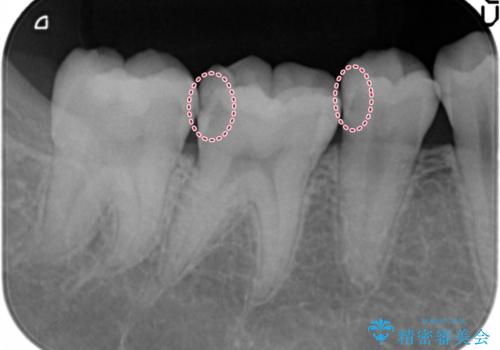

隠れているむし歯 セラミックインレーによる治療

- 2年ぶりの来院。メンテナンス時に虫歯が多数確認されました。

まずは虫歯の大きいところから治療を進めることになり今回は右下の奥歯の治療を行いました。

- 右下56 セラミックインレー 77000円×2本費用は治療当時の料金となります

メンテナンスで虫歯を発見することができたため、症状が出る前に治療を終えることができました。下の奥歯は笑った時に外からよく見える部分なので白く目立たない詰め物を入れることができて大変喜んでいただけました。

放置していくとインレーでの修復が難しくなってしまうため、定期的なメンテナンスが大事になってきます。